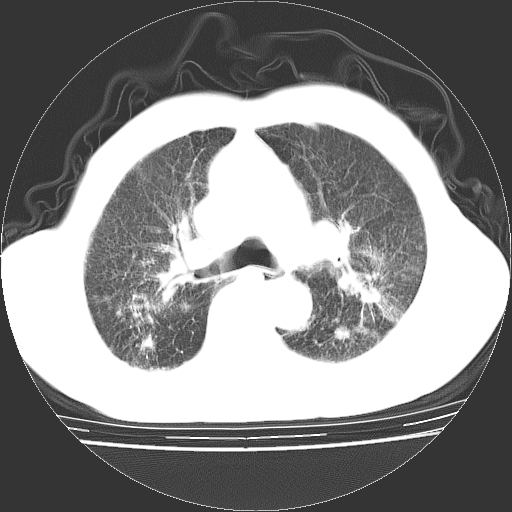

男,72岁,反复咳嗽、憋气一年余,有15年的煤矿井下工作史。

1、双肺中上叶结节影结合病史考虑巨块型矽肺结节。

2、慢支炎并肺气肿

3、双下肺纤维化灶并左下肺局限性肺气肿。

支持 尘肺,肺心病?-------15年的煤矿井下工作史,双上肺叫对称的片团结节影,内见斑状钙化,边缘见粗长毛刺影,肺纹理混乱,可见网状及磨玻璃样影,肺门纵膈见多个淋巴结钙化